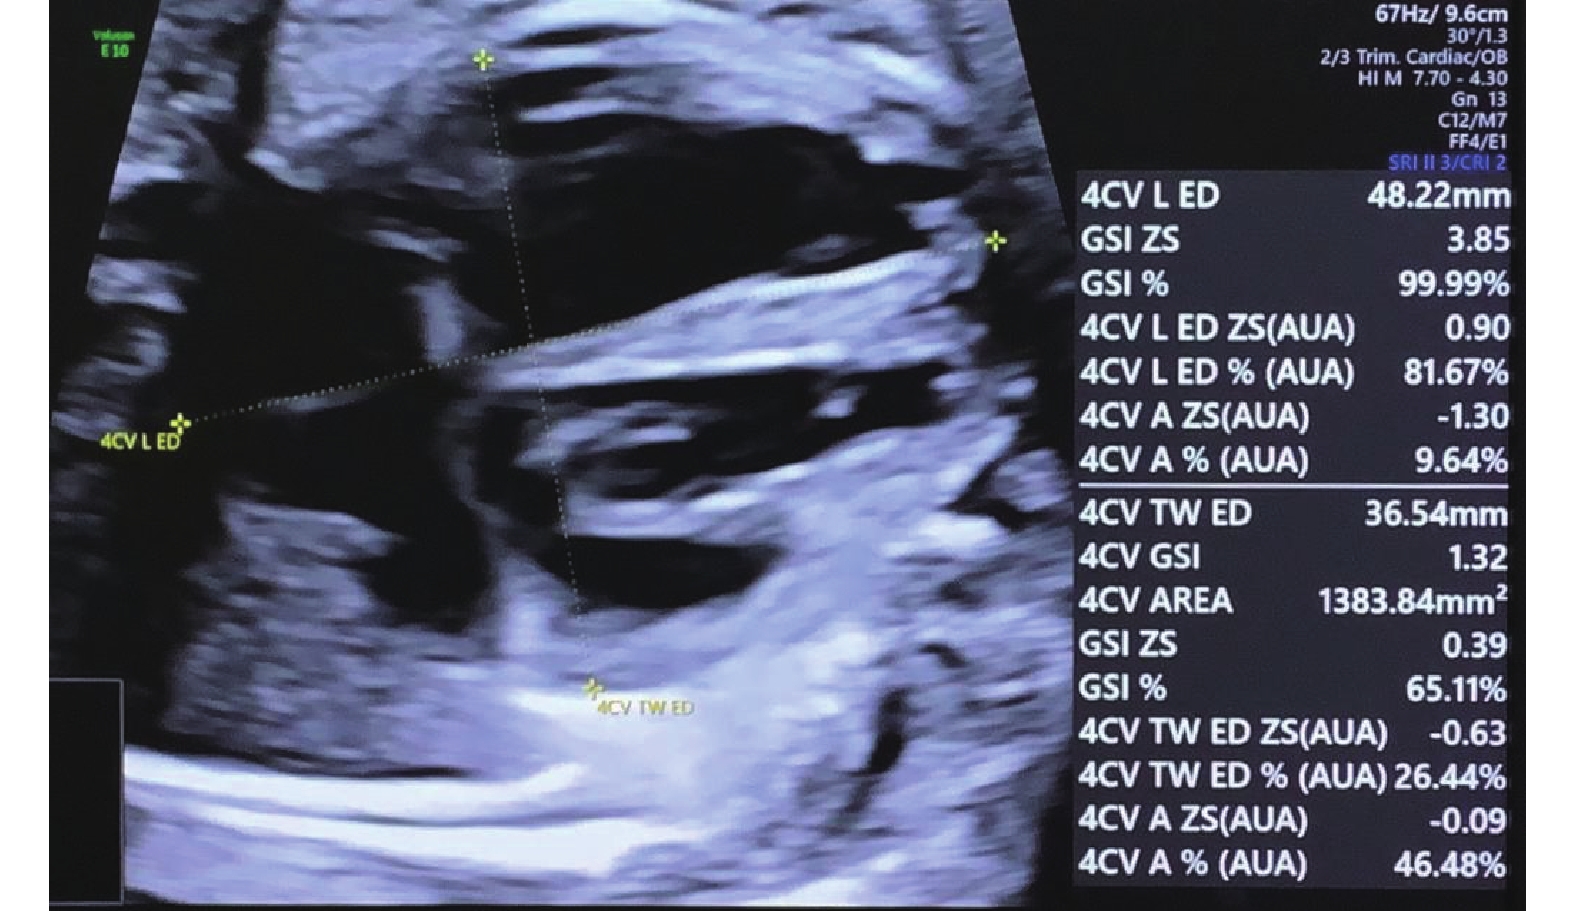

Figure 6

Measurement of the fetal cardiac GSI. A longitudinal line is drawn from the apex to the base of the cardiac outer edge, and a transverse line is drawn from the sidewall of the LV to the sidewall of the RV at the end of the diastole. The GSI can be obtained by dividing the end-diastolic basal–apical length by the end-diastolic transverse width. GSI, global sphericity index; LV, left ventricle; RV, right ventricle. (Images were acquired on E10 Voluson ultrasound machine and analysed using FetalHQ software)"